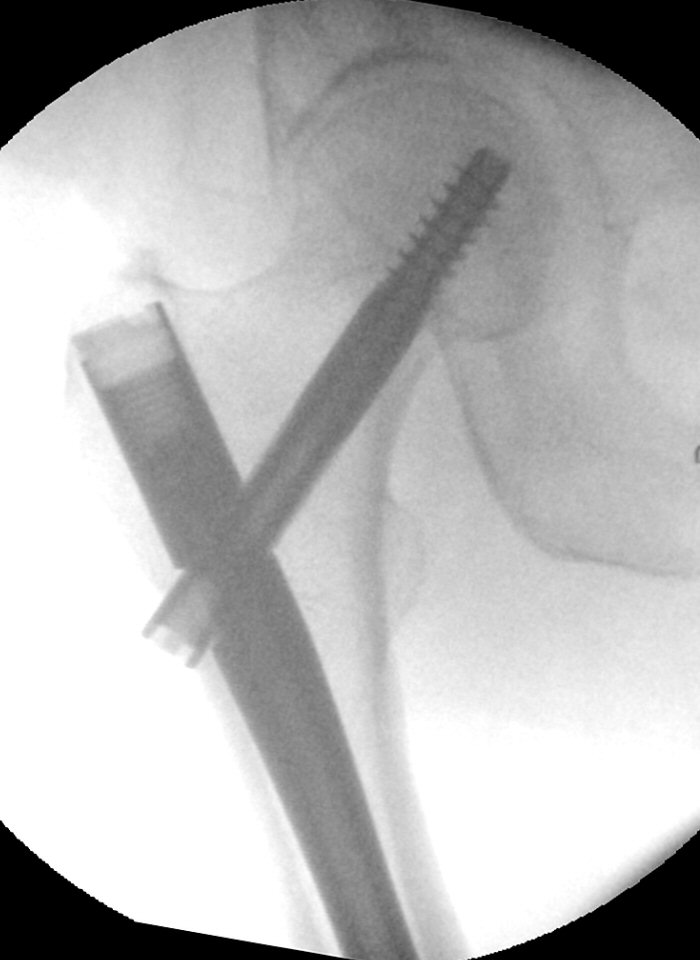

- Flytta genomlysningen, rotera benet så man kan lysa rakt igenom märgspikens distala låshål.

- Borra hål för distala låsskruvar. Antingen:

- Lokalisera låshålen, gör snitt i huden.

- Använd pryl i genomlysning för att markera i femur var låsskruvarna ska sitta.

- Använd icke röntgentät vinkelborrmaskin och borra hålen - kontrollera i genomlysning.

- Eller:

- Se till att sidobilden är exakt rak, man kan behöva rotera röntgenapparaten. Det runda hålet i spiken ska vara runt, och det avlånga hålet ska vara avlångt, utan några dubbelkonturer.

- Markera i frontalvy exakt var mitten av hålet är

- Markera i sidobild exakt mitten av hålet, använd gärna kniv

Knivspets markerar placering av statisk distal låsskruv. Notera att bilden är tagen exakt rakt från sidan.